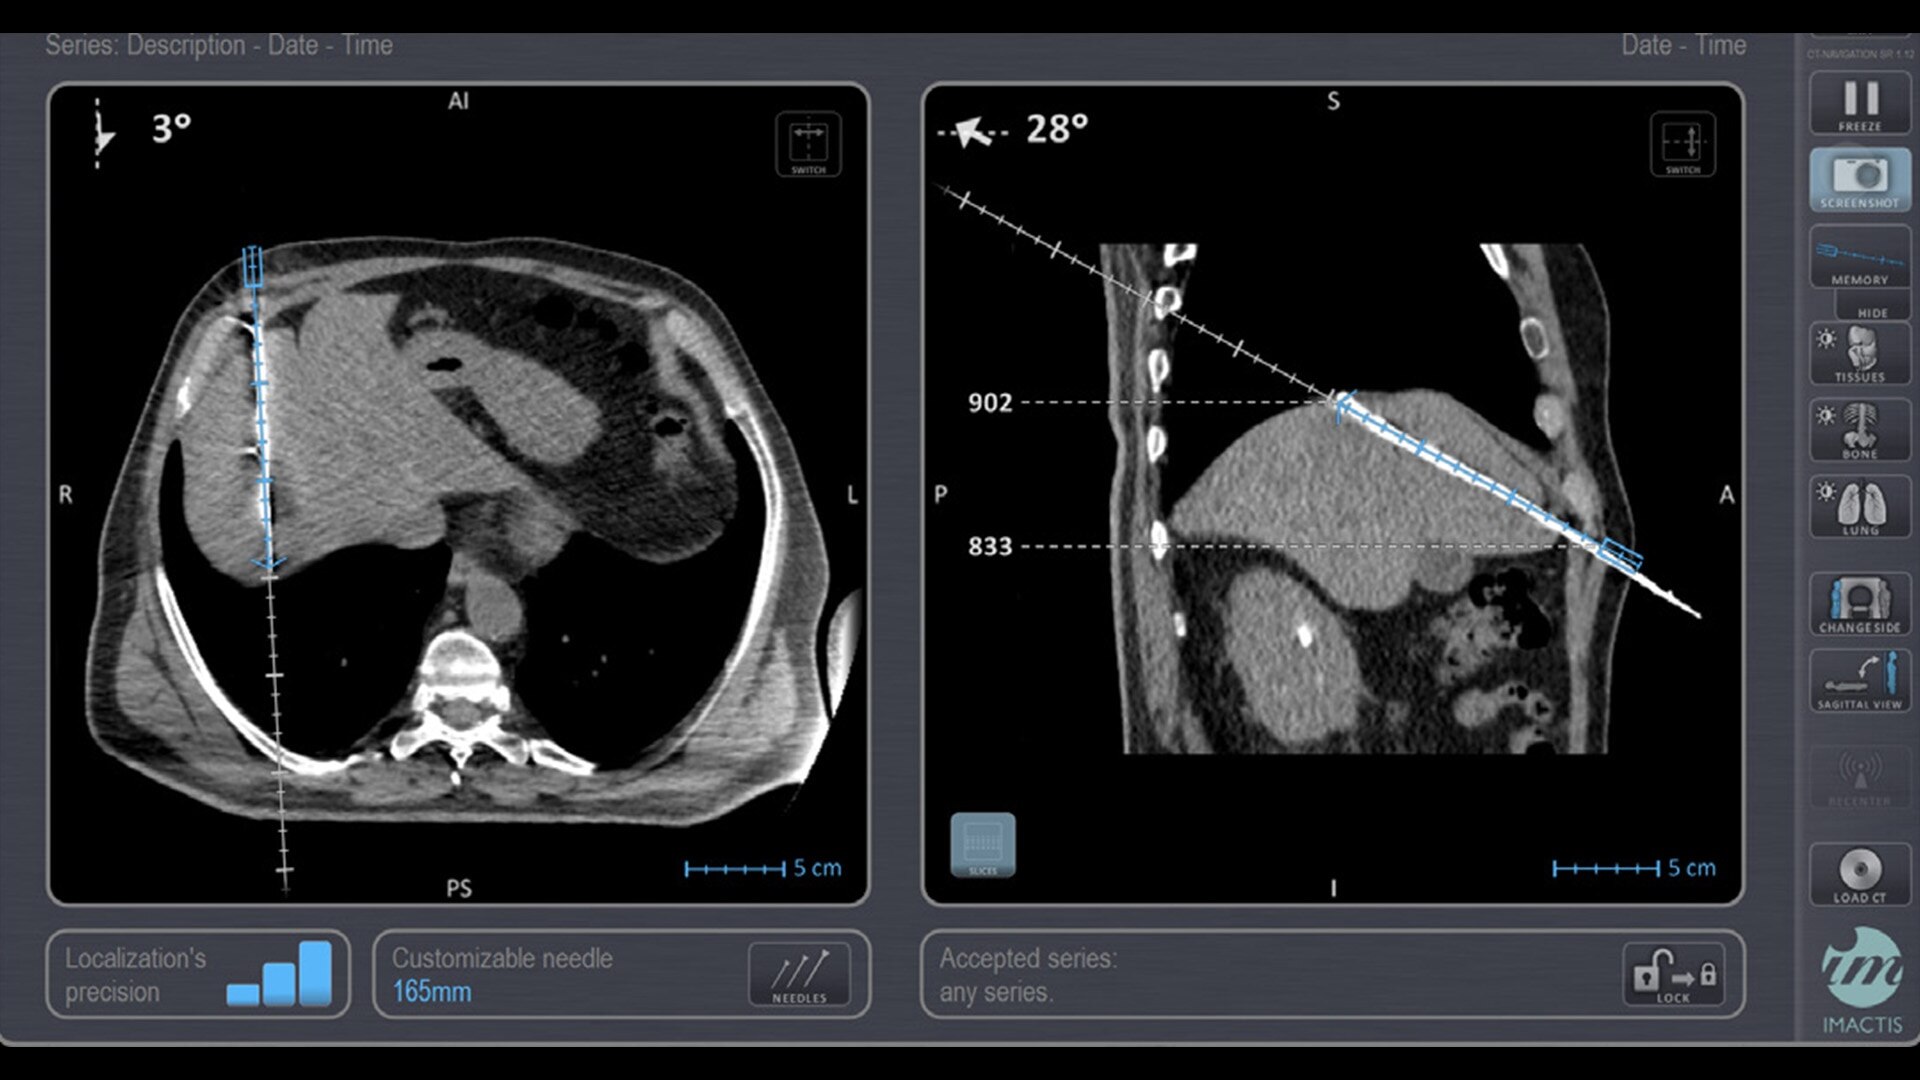

Imactis® CT-Navigation™

Planning and navigation solution for interventional percutaneous radiology that can increase procedure accuracy, reduce time, simplify workflow and reduce dose.¹

In interventional radiology, the success of the percutaneous procedure depends on correct needle positioning. The Imactis system helps the radiologist place one or more needles with great accuracy, in less time and with fewer control scans.

Accuracy

Imactis enables you to find the ideal path to the target.

With real-time image reconstruction, live interactive navigation and no limit in angulation, the optimal clinical choices are clear.

Live 3D needle tracking, precise reproduction of your planned trajectory and continuous needle depth measurement help ensure optimal needle placement.